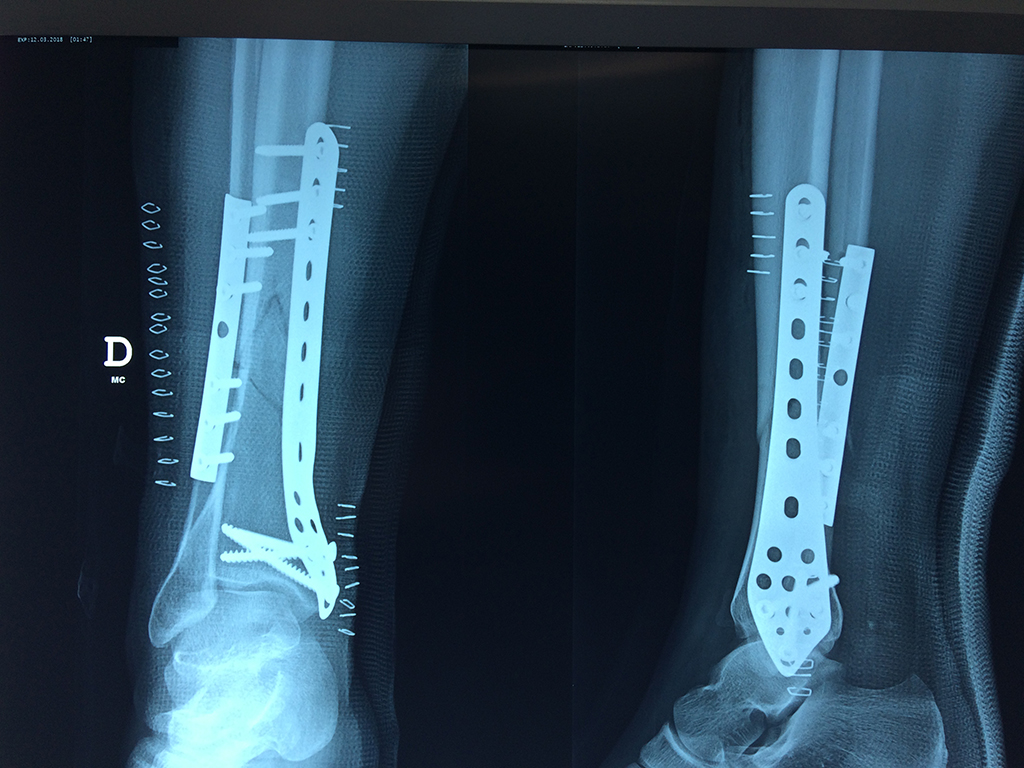

La mayor parte de las roturas implican a la parte proximal del hueso (parte del hueso próximo a la rodilla) o a la parte distal (parte del hueso cerca del tobillo).

Debido a la fina cobertura de piel que recubre la tibia y el peroné, las fracturas generalmente son abiertas, es decir, el hueso roto rasga la piel, atravesándola. Las fracturas de tibia y peroné generalmente se producen por un fuerte impacto o torsión.